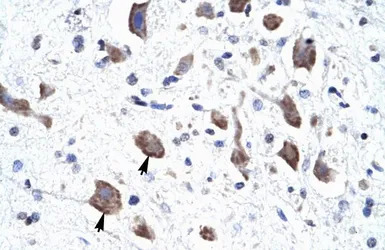

IHC-P analysis of human brain tissue using GTX47617 CLCN3 antibody at 4.0-8.0μg/ml.